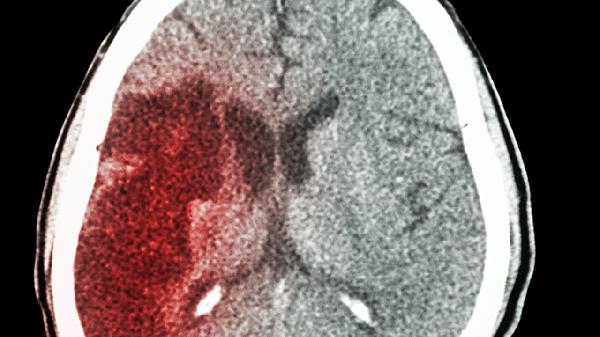

脑梗这个"隐形杀手"最喜欢在清晨搞突袭!你知道吗?医院急诊室的统计显示,早上6-10点脑梗发作率比其他时段高出3倍。别以为这是老年人的专利,现在30多岁的上班族中招的也不少。其实预防脑梗没想象中复杂,关键是把好"晨起"和"睡前"两道关。